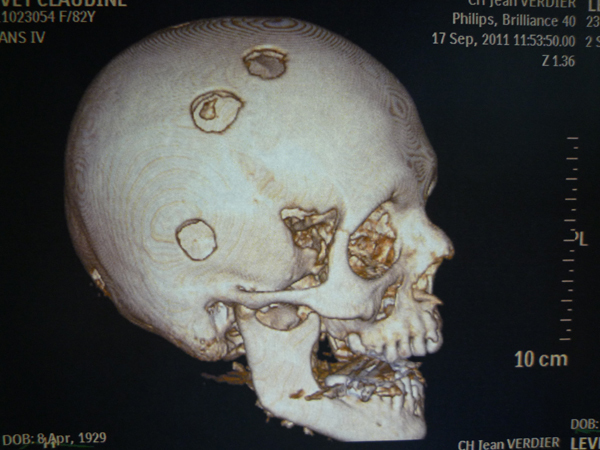

Quel est votre diagnostic ?

Il s'agit de métastases d'un carcinome d'origine inconnue.

Cette photo provient de la collection du Pr Olivier Fain (Bondy)